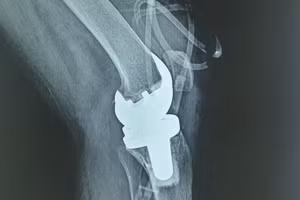

GD&TĐ - Lần đầu tiên tại miền Trung, công nghệ robot tích hợp AI được ứng dụng trong phẫu thuật thay khớp gối tại Vinmec Đà Nẵng, không chỉ nâng cao độ chính xác mà còn mở ra khả năng phục hồi ấn tượng khi bệnh nhân có thể đứng dậy, tập đi ngay sau mổ - điều trước đây là thách thức, đặc biệt với người cao tuổi.